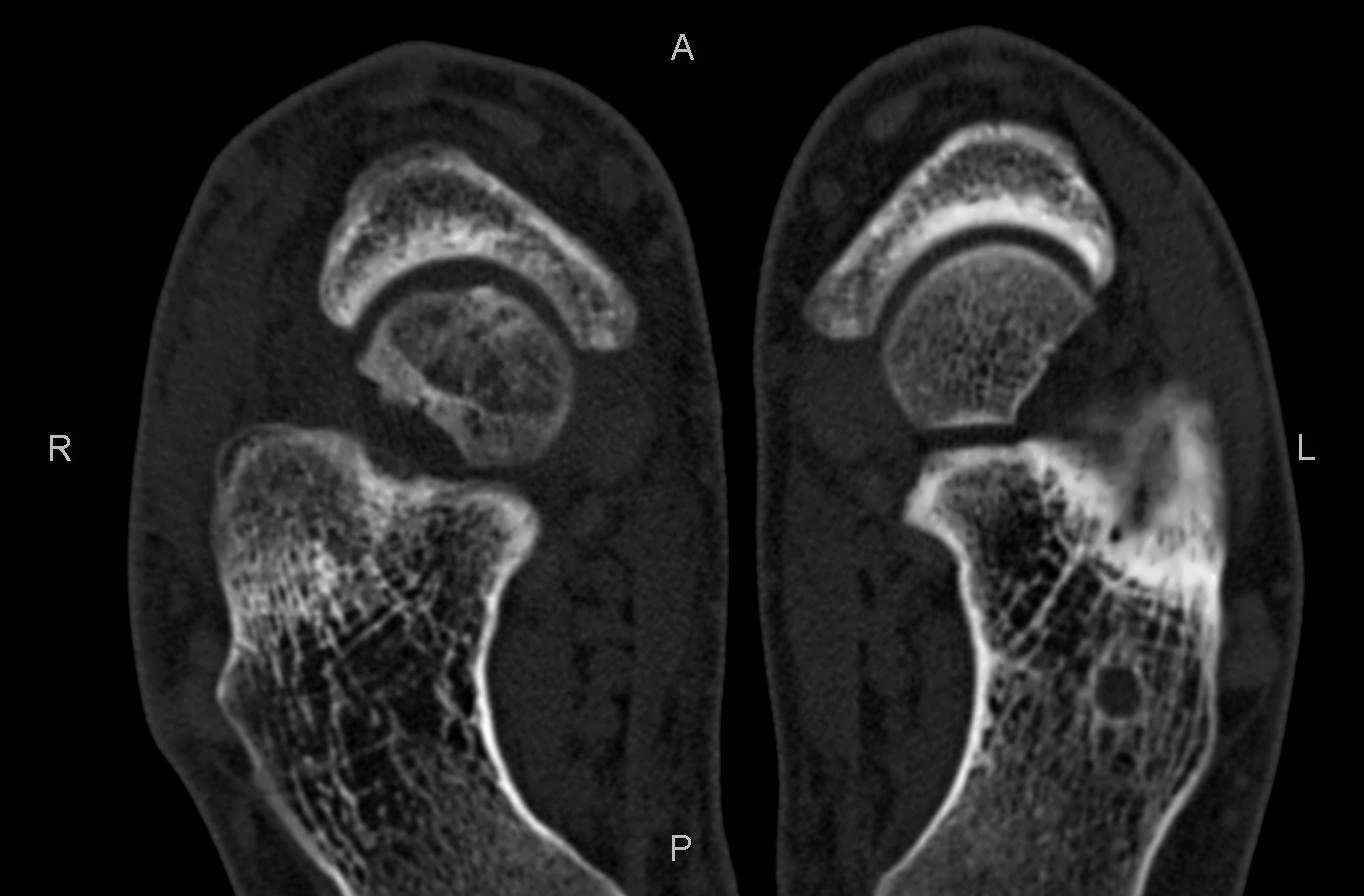

Уважаемые коллеги, обратился за помощью пациент, мужчина, 25 лет. С жалобами на болевой

синдром в области голеностопного сустава и среднем отделе стопы. Травму отрицает. Со слов,

болевой синдром в течении 1 года. Последние 1-1.5 мес периодически вынужден пользоваться

костылями. После ограничения нагрузки боли уменьшаются. Соматически здоров. До появления

болей активно занимался рукопашным боем.

На СКТ картина рассекающего остеохондрита блока

таранной кости, киста шейки таранной кости с признаками импрессии суставной поверхности. А

также - разрастания переднего края б\берцовой кости сопровождающиеся клиникой импиджмент

синдрома.